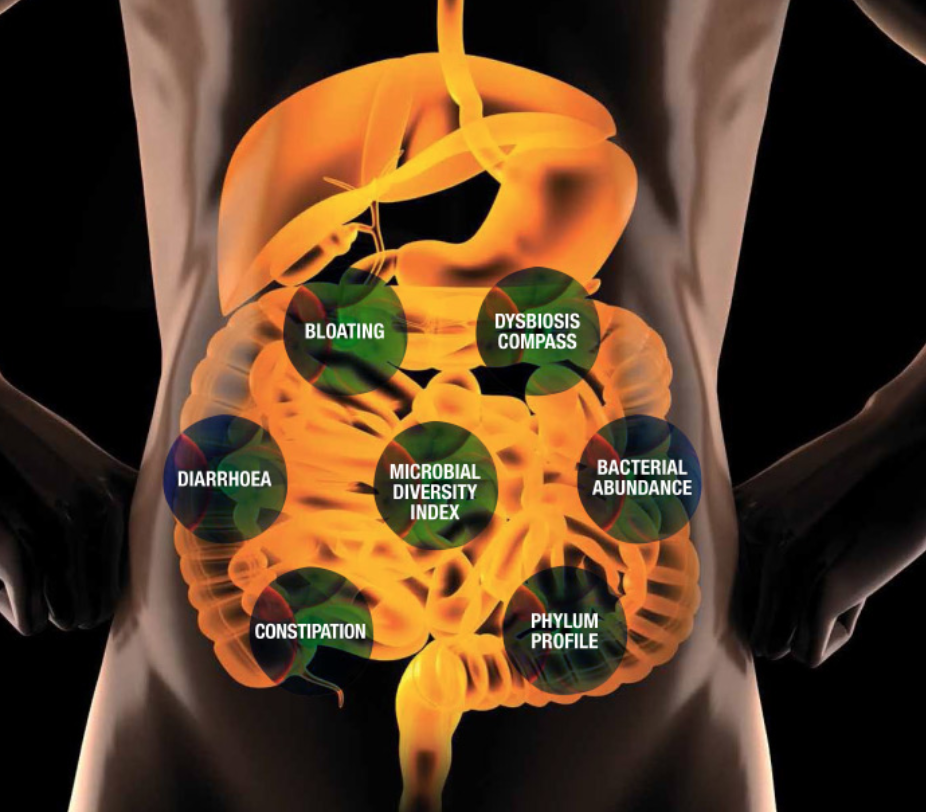

Microbiome Test

IBS GUT

Detector

GUT Spectrum

Detector